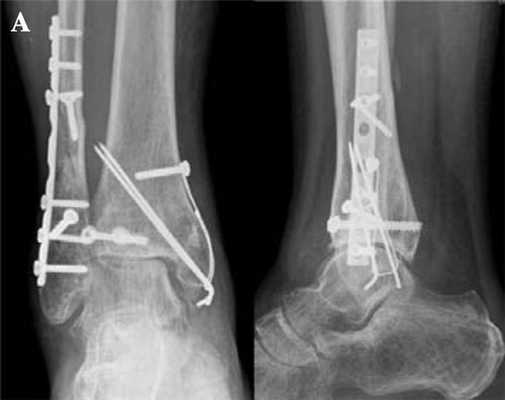

Предоперационное планирование

- Рентгенологическое обследование пациента, выявление рентгенологических признаков остеоартроза плюснефалангового сустава.

Операция

Положение больного на спине. Выполняется медиальный доступ к первому плюснефаланговому суставу. Резецируется 5-6 мм основания основной фаланги первого пальца, головка первой плюсневой кости. Резекция выполняется строго по продольной и вертикальной осям по резекционным блокам. Готовится ложе для компонентов эндопротеза.

При помощи импактора методом «пресс-фит» устанавливается плюсневый компонент. На порции костного цемента устанавливается фаланговый компонент в положении сгибания первого пальца. Сустав вправляется, проверяется объём движений. Контролируется гемостаз. Рана послойно ушивается. Бинтовая повязка.

Через 2 недели разрешается нагрузка на оперированную конечность. Через 6 недель выполняется контрольная рентгенография, оценка активных и пассивных движений. Окончательный результат оценивается через 6 месяцев после операции.